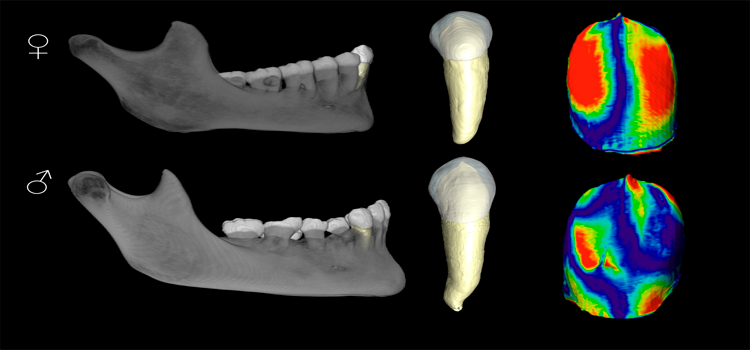

Los caninos revelan nuevas claves para la estimación del sexo de poblaciones humanas

Un estudio del Grupo de Antropología Dental del CENIEH describe las principales diferencias morfológicas existentes en las estructuras internas de los colmillos de hombres y mujeres de poblaciones actuales y destaca la utilidad de esta pieza dental para la creación de perfiles biológicos